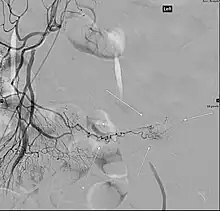

Angiography of a Meckel's diverticulum that presented with bleeding.

Angiography might identify brisk bleeding in patients with Meckel's diverticulum.[21]